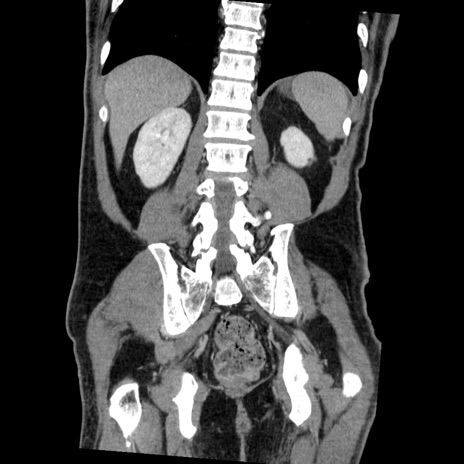

症例22(冠状断像)

【症例】50歳代男性

【主訴】腹痛

【現病歴】AVMからの被殻出血のため回復期リハ病棟入院中。 本日午後3時頃急に下腹部痛が出現した。

【既往歴】AVM、被殻出血、虫垂炎、高血圧

【身体所見】意識晴明、左半身不全麻痺、会話の理解は良好、36.5°C、腹部:膨隆、全体に板状硬、下腹部正中に圧痛点あり、反跳痛-、筋性防御不明、右下腹部にope scar

【データ】WBC 9400、CRP 0.06